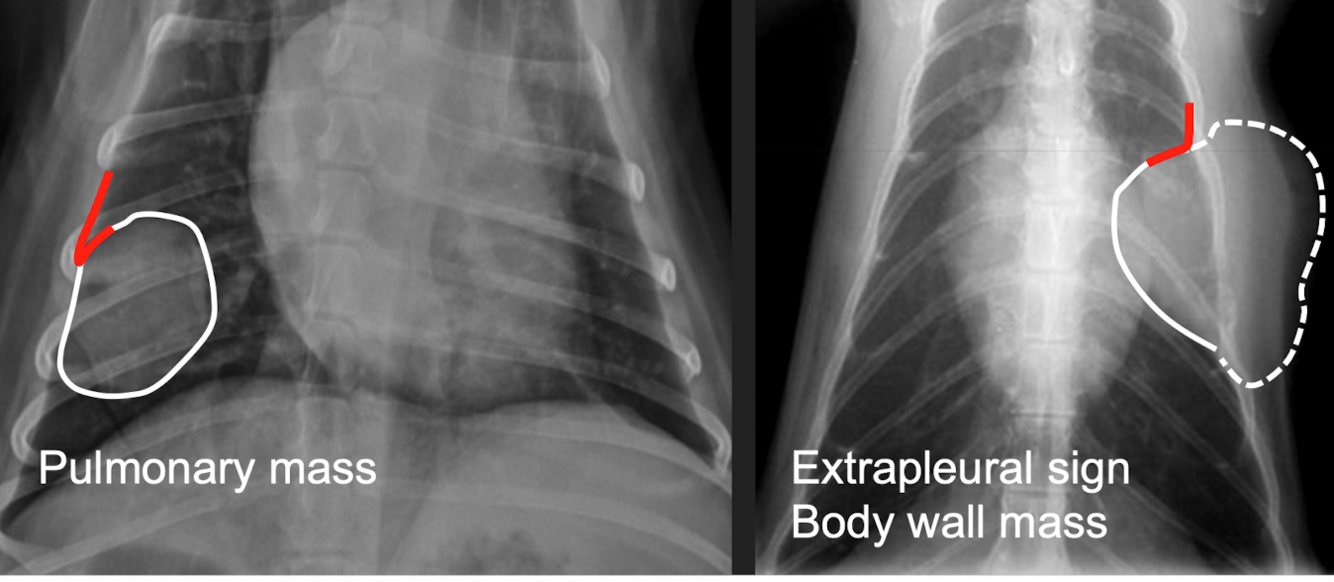

extrapleural mass/signs will have — on xrays

Broad-based mass on the chest wall

Convex shape

Lungs displaced medially

+/- Uneven distances between ribs

+/- Lysis of ribs

Most often neoplasia

which one pulmonary mass vs extrapleural sign

extrapleural sign: